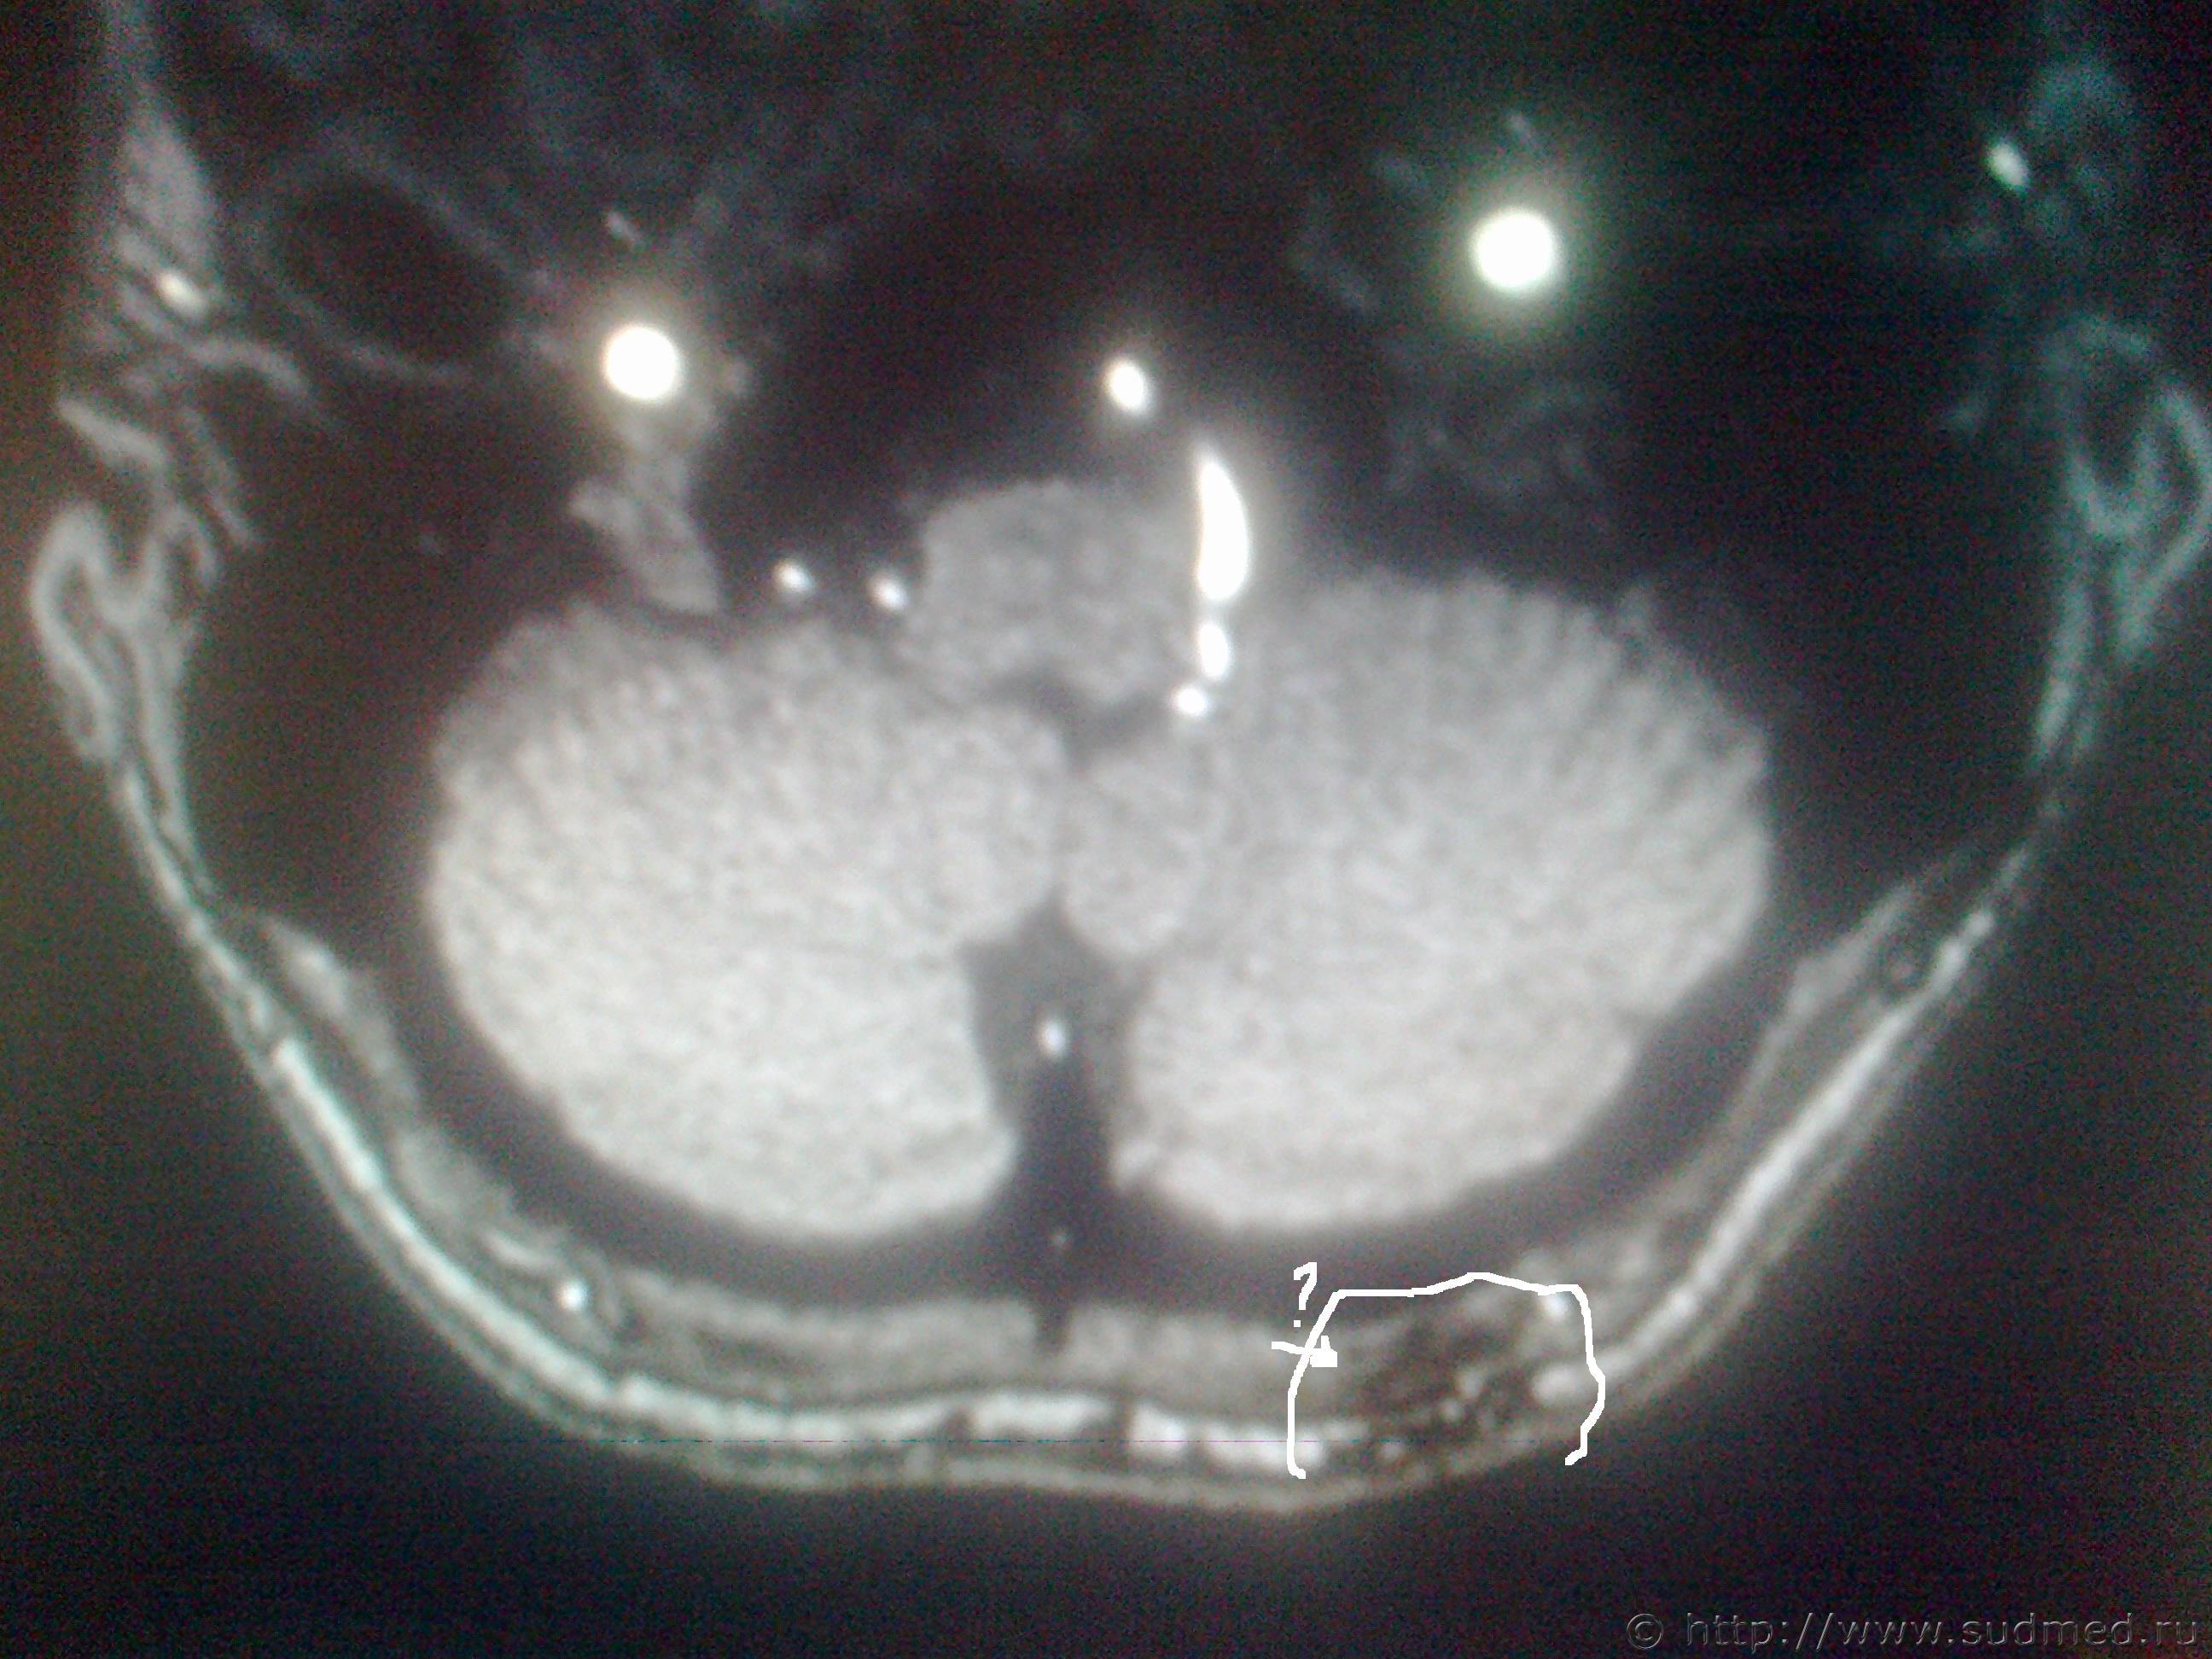

Оч. важно ваше мнение ув. специалисты! В анамнезе травма,на снимках деструкция кости, местно в этой области гиперемия (покраснение). СНИМКИ ПО КОТОРЫМ ВЫСТАВЛЯЮТ ДИАГНОЗ ПРИЛАГАЮ

Эскизы прикрепленных изображений

Судебная медицина - Прикрепленное изображение Судебная медицина - Прикрепленное изображение